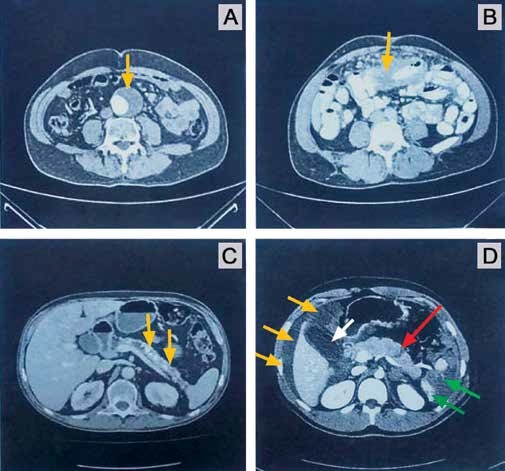

Dentre as tomografias computadorizadas de abdome demonstradas, qual é a mais compatível com o caso apresentado? É realmente isso que o enunciado deseja saber. Fica aqui uma dica: quando avaliamos uma questão com imagem de exames complementares radiológicos, antes de “partirmos direto” para a imagem propriamente dita, é fundamental que leiamos com muito cuidado a história clínica descrita. Nosso paciente foi vítima de contusão abdominal, consequência de impacto de bicicleta contra um anteparo fixo, na realidade houve choque do abdome superior contra o guidão da bicicleta. De objetivo na avaliação inicial do paciente: encontra-se hemodinamicamente estável, taquicárdico e com dor a palpação em mesogástrio e epigástrio, onde há sinais de escoriações e equimoses. A taquicardia pode representar tanto perda volêmica discreta, quanto ser ocasionada por dor. Recebeu 2.000 ml de cristaloides e analgesia. Manteve pressão arterial estável e houve redução da frequência cardíaca. Agora, vamos lá: na imagem A nós temos um aneurisma de aorta abdominal com trombo mural (seta amarela) como principal achado; na imagem B chama a atenção alça espessada (seta amarela); e na imagem C reparem que há múltiplas calcificações pancreáticas (setas amarelas), o que denota uma pancreatite crônica, sem dúvida alguma. A imagem D é compatível com a história descrita. Vejam uma imagem bastante hipodensa em topografia de baço, sem definição de cápsula esplênica, onde há também extravasamento de contraste (alterações presentes em setas verdes), ou seja, temos um parênquima esplênico bastante comprometido (pulverizado?). As setas amarelas correspondem ao líquido livre em cavidade, que em uma topografia mais superior se infiltra por sobre o fígado também (não é hematoma hepático!). Até aí entendemos esses achados – o trauma esplênico foi o responsável por esse líquido livre (na realidade um hemoperitônio). A taquicardia pode realmente ter representado essa discreta perda volêmica (hemorragia classe I). Além destes achados, temos uma imagem hipodensa linear em corpo de pâncreas (seta vermelha), o que traduz uma laceração corpocaudal pancreática. O mecanismo dessa lesão foi a compressão do corpo do pâncreas entre o guidão da bicicleta e a coluna vertebral. Podemos concluir, sobretudo com essa lesão pancreática, que o paciente foi vítima de uma contusão abdominal realmente intensa. Observamos também nessa tomografia computadorizada imagem de vesícula biliar distendida (seta branca), o que não tem importância alguma para o caso (jejum prolongado?).